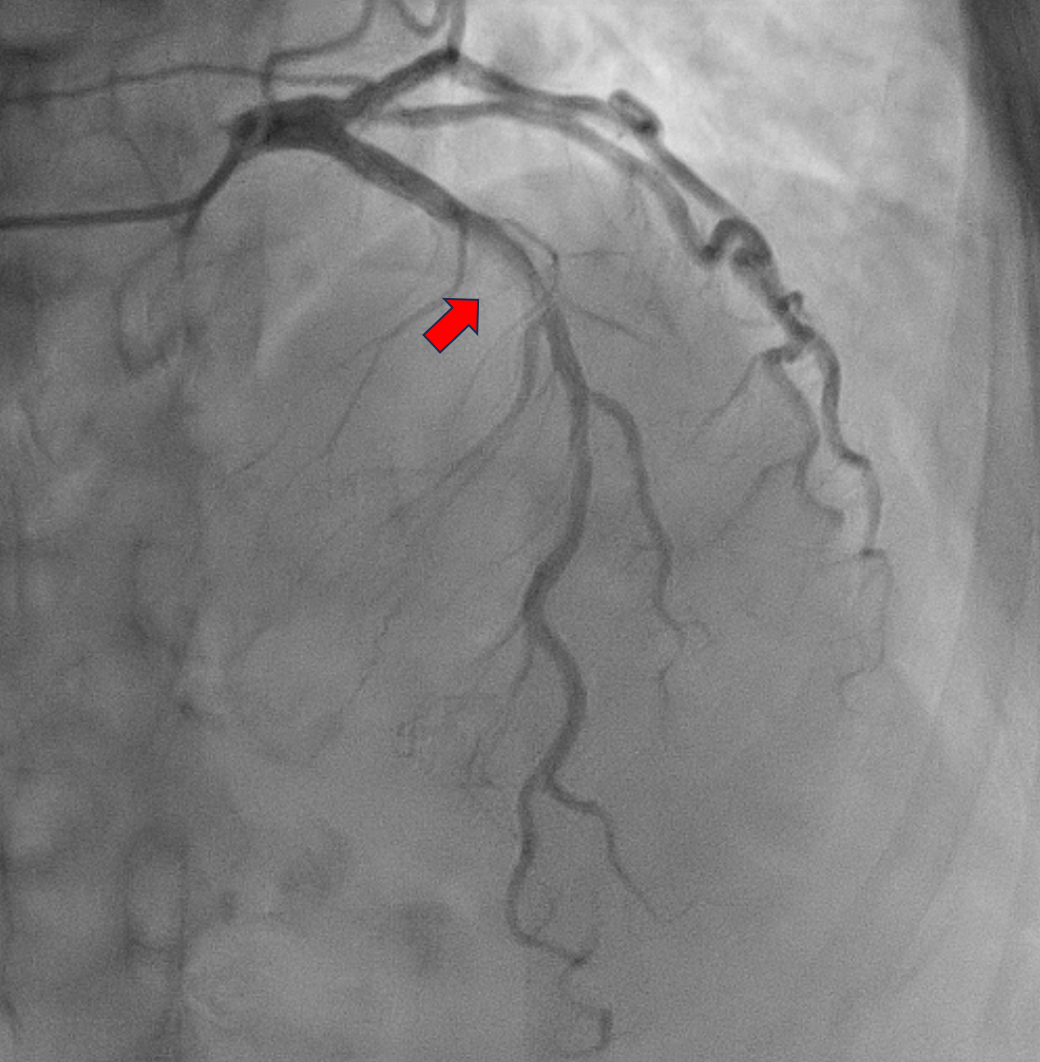

Relevant Catheterization Findings

The patient was electively admitted for diagnostic coronary angiography on August 12, 2024, which revealed single-vessel disease (SVD) with 95% stenosis in the proximal to mid left anterior descending (LAD) artery. The LAD lesion is tight and calcified. His Left circumflex vessel and right coronary vessel are normal. We proceeded with percutaneous coronary intervention (PCI) to the LAD with DCB only strategy.

The procedure was performed using a 7 Fr right radial approach. A total of 6000 units of intracoronary heparin and 300 mg of oral clopidogrel were administered. The left coronary system was engaged with a 7 Fr extra-backup (EBU) 3.5 mm guiding catheter, and the lesion was successfully crossed with a Run-through floppy wire extending to the distal LAD. Pre-dilation was performed with a 2.0 mm x 15 mm Genoss balloon, inflated to 16 atm. Intravascular ultrasound (IVUS) imaging revealed 360-degree superficial calcium at the tight LAD lesion, a vessel diameter under 3.5 mm, and a calcium score of 2. The mid-LAD measured 3.0 mm and the proximal LAD measured 4.0 mm. Pre-dilation was performed in the mid-LAD using a 3.0 mm x 16 mm Genoss non-compliant (NC) balloon, and in the proximal LAD with a 3.5 mm x 20 mm NC Emerge balloon, both inflated to 16 atm. Post-pre-dilation IVUS imaging showed cracking of the superficial calcium with vessel expansion to 3.0 mm. Subsequently, drug-coated balloon (DCB) angioplasty was performed with a 3.0 mm x 30 mm Magic Touch DCB in the mid-LAD and a 3.5 mm x 35 mm Magic Touch DCB in the proximal LAD. Final angiography demonstrated a non-flow-limiting Type A dissection with less than 30% recoil, and the procedure was successfully concluded.